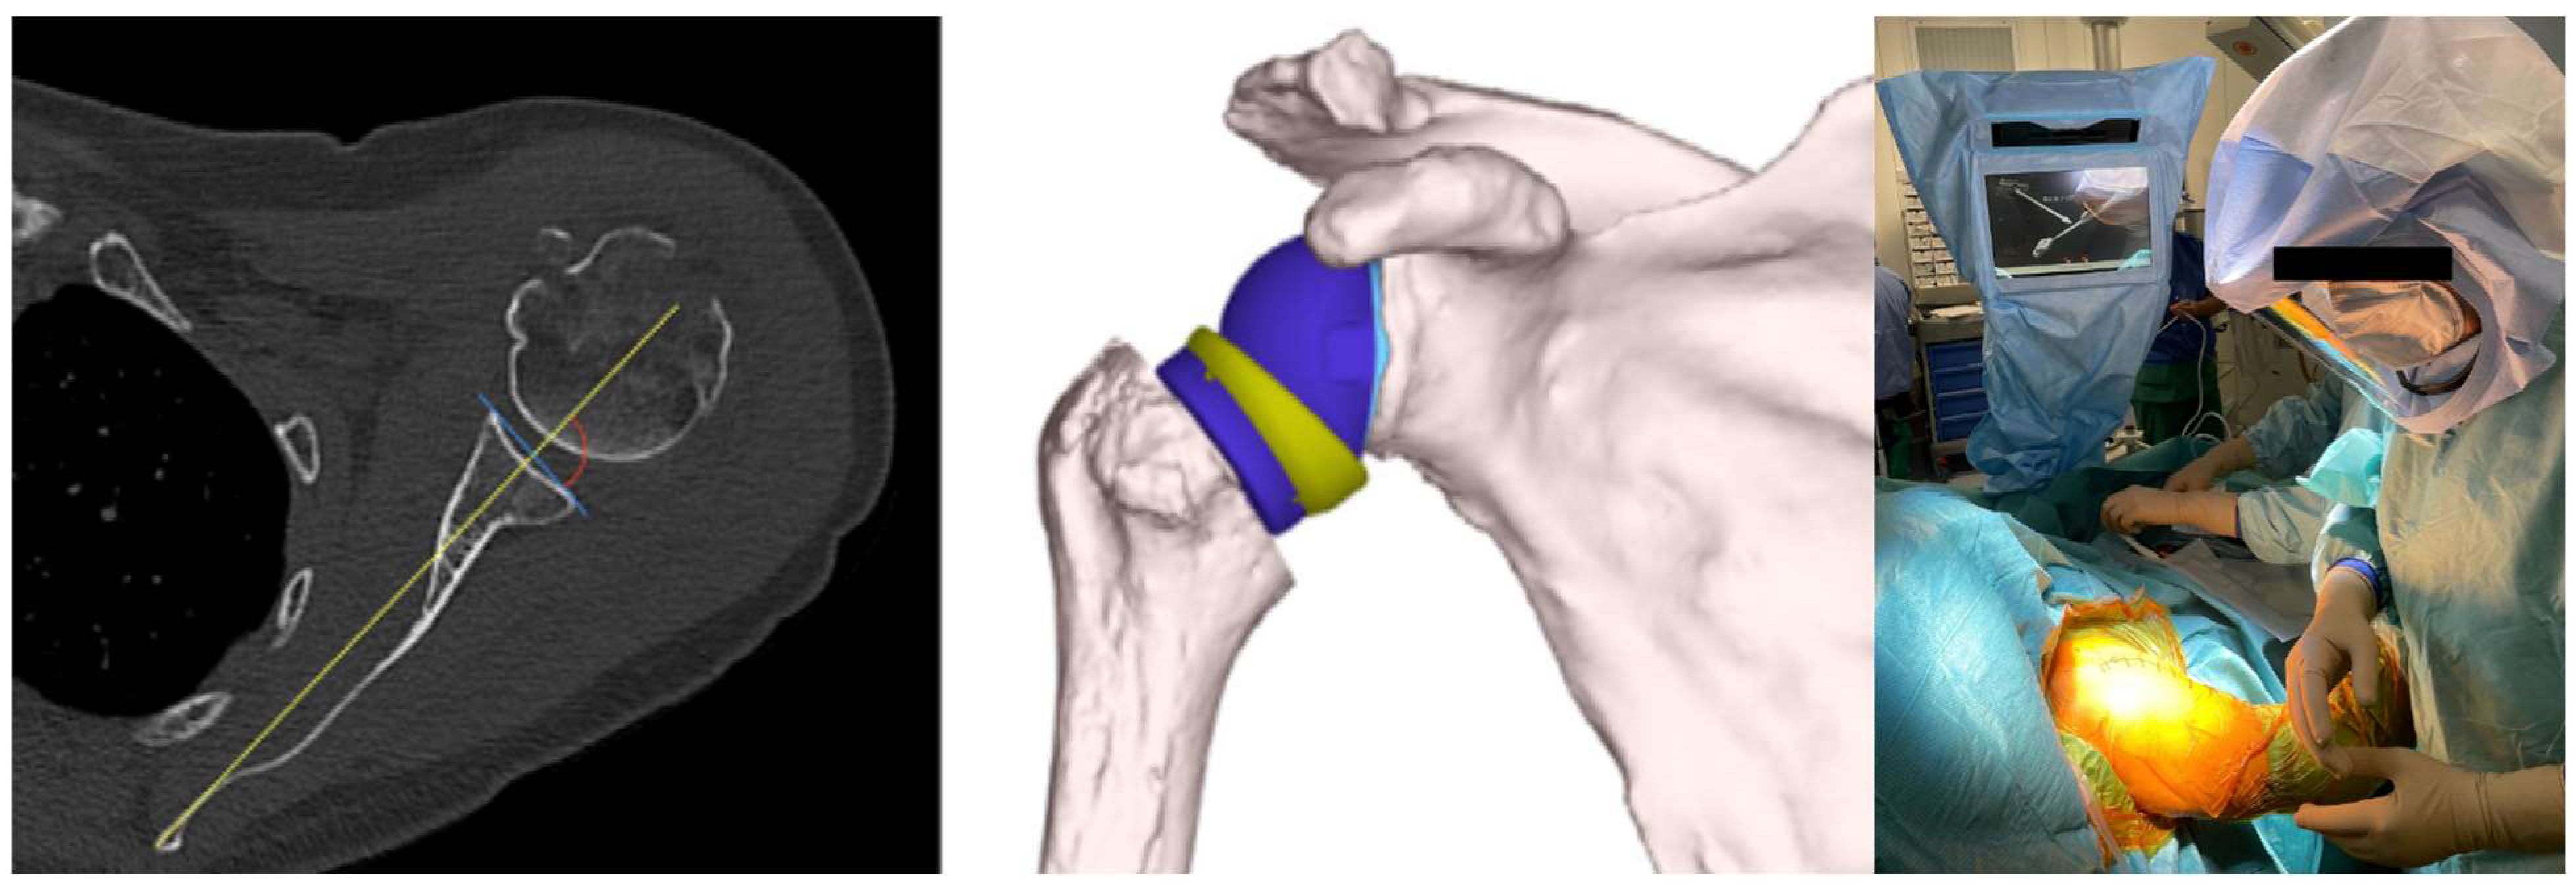

Using the Orthoblue software—Equinoxe Shoulder Planning App (Exactech, Gainesville, FL, USA), the glenoid component can then be virtually positioned within the 3D rendering of the patient’s scapula before surgery begins. It is easy to visualize the version, inclination, and positioning of the glenoid implant, evaluating the need for augmentations, increasing and compensating for the inclination and version. It is also possible to determine the measurement of the lateralization and elongation of the humeral stem in relation to the acromion and the native glenoid rotation center and compare them with the measurements corrected by the proposed implant. In addition, it is possible to evaluate the size of the glenosphere, the lateralization and the size of the insert, the range of motion, and, thus, the excursion of the humerus on the scapula in terms of adduction and abduction, internal and external rotation, anterior elevation, and retroposition of the proposed implant (Figure 1).

Figure 1. The surgical procedure for reverse shoulder arthroplasty with GPS navigation involves a preoperative CT scan, planning, and intraoperative navigation.